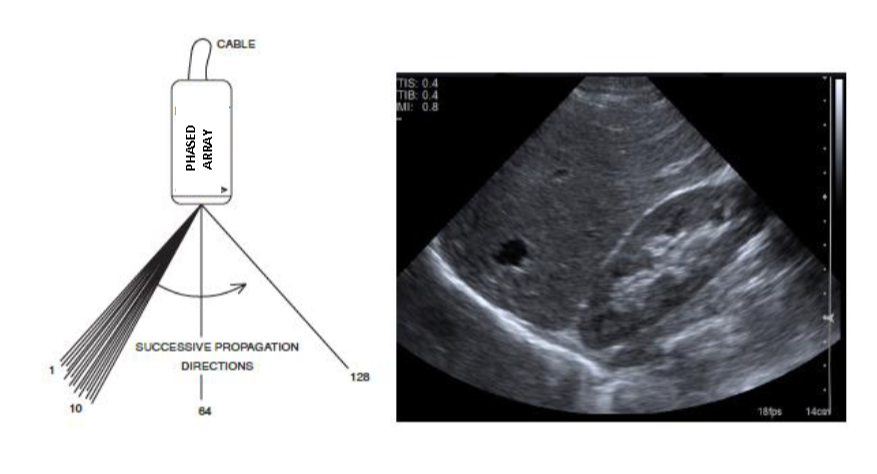

Diagram of a sector transducer (left) shows successive lines of propagation sweeping from left to right and numbered 1 through 128. The sector shape of the image on the display is shown on the right.